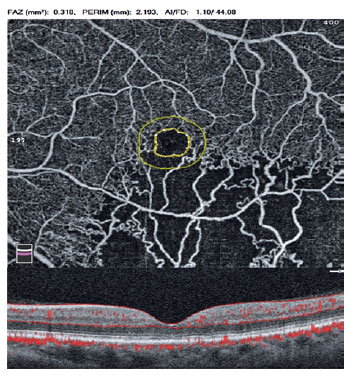

Seven horizontal scans through the fovea and a 120-µm B-scan spacing were performed on the high-resolution mode of SD-OCT (Spectralis; Heidelberg Engineering) by a technician. DRIL was defined as the horizontal extent in microns for which any boundaries between the ganglion cell-inner plexiform layer complex, inner nuclear layer, and outer plexiform layer were indistinguishable(7). Measurement of the DRIL extent through the fovea was retrospectively performed by two masked observers (Figure 1). The average of the measurements was used to derive a global DRIL measurement for the eye.

06-fig01.jpg)